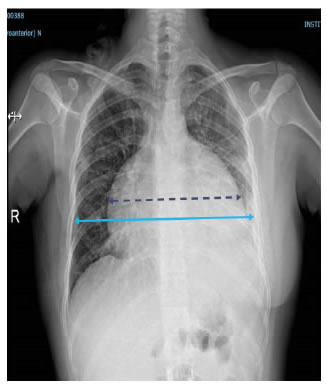

En el electrocardiograma se encontraron signos de bajo voltaje y ausencia de la onda p. En la radiografía de tórax se observó ensanchamiento de la silueta cardiomediastínica y borramiento del ángulo costofrénico izquierdo (figura 1). En la tomografía de tórax (TC), se observó un derrame pericárdico con separación de 3,5 cm entre las hojas del pericardio y un derrame pleural izquierdo (figura 2).

El drenaje pleuro-pericárdico temporal se mantuvo durante tres semanas hasta que los gastos fueron menores de 50 ml. La radiografía de tórax mostró la posición del catéter pleuropericárdico, una adecuada expansión pulmonar izquierda y disminución del tamaño de la silueta cardiomediastínica (figura 4). La paciente recibió rehabilitación cardiopulmonar (figura 5).